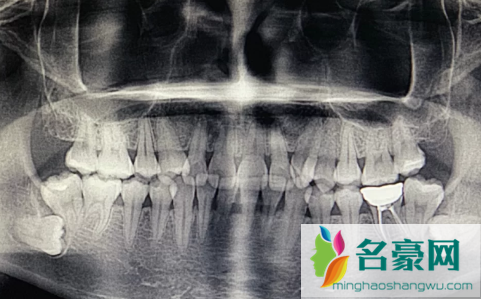

现在很多人都爱长智齿,去医院洗牙或者检查牙齿时,医生都会建议拔掉智齿,毕竟会引发其他牙齿的生长或引起炎症问题。那么,大医院的牙科和专门的牙科医院哪家好?这个看个人选择,都是正规的医院。

牙医建议拔掉智齿主要是因为牙齿反复发炎,会影响邻近的牙齿。

1、反复炎症:智齿出牙不完整,龈冠覆盖后侧部分形成冠周袋。不注意个人卫生,局部软组织往往会发炎,出现疼痛症状,所以需要拔掉智齿才能有效改善。

2、影响邻近牙齿:如果牙齿生长位置不正确而拥挤,就有可能对邻近牙齿造成损害,使咀嚼功能严重受损,因此需要拔除智齿。